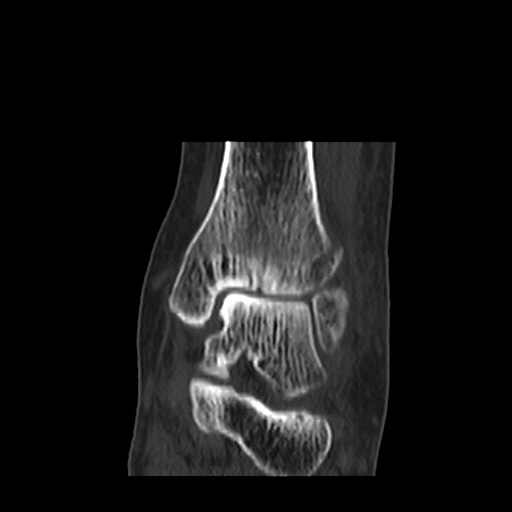

[¹ß¸ñ] distal tibiofibular ligament sprain with avulsion fracture of tibia

CT : avulsion fracture of distal tibia at distal tibiofibulat ligament insertion.